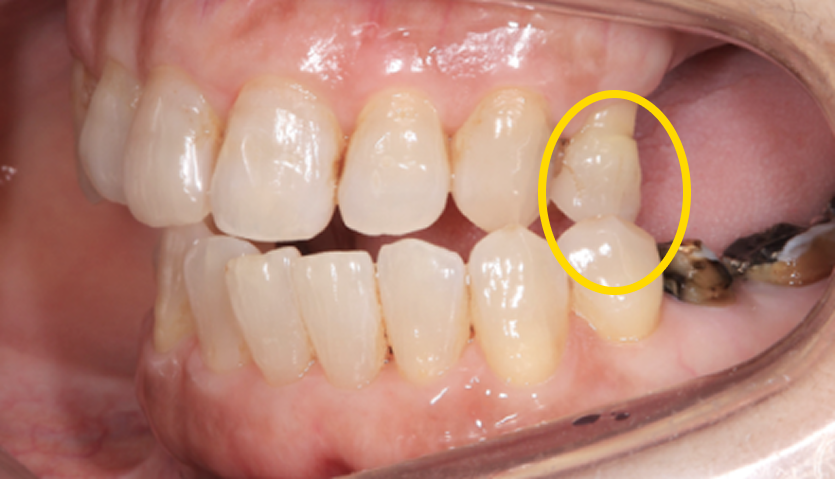

この歯(黄色の印)は顎を横に動かした時に強い力が加わり、歯の周囲の組織にダメージが出ているため、力をコントロールするために歯の形を修正が必要です。

右の奥歯についても歯が伸びてしまっているのでこちらは部分的な矯正治療と歯茎の手術で対応しています。